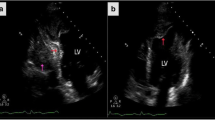

The measurement of CVF was shown in Table 2 and Fig. 4. MPM-derived CVF was comparable to that derived from picrosirius red staining based on all samples (22.58 ± 11.13% vs. 21.19 ± 11.79%, p = 0.348), as well as in DCM samples and ICM samples (Fig. 4a). Patients with ICM had significantly greater MPM-derived CVF (25.33 ± 12.65% vs. 19.82 ± 8.62%, p = 0.006) and staining-derived CVF (24.48 ± 13.20% vs. 17.89 ± 9.18%, p = 0.002) than patients with DCM (Fig. 4b).

Comparisons of CVF based on different measurement modalities and cardiomyopathies. The CVF measured by MPM was comparable to that measured by picrosirius red staining, regardless of the type of cardiomyopathies (a). The CVF in ICM patients was slightly higher compared with that in DCM patients, regardless of the measurement modalities (b) ICM, ischemic cardiomyopathy; DCM, dilated cardiomyopathy; other abbreviation as in Fig. 3